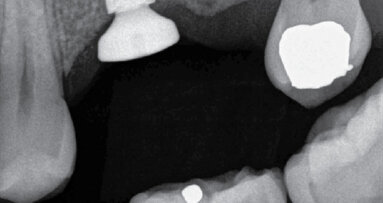

Po důkladném zprůchodnění a mechanicko-chemickém opracování kořenových kanálků byly tyto hermeticky zaplněny (obr. 8).